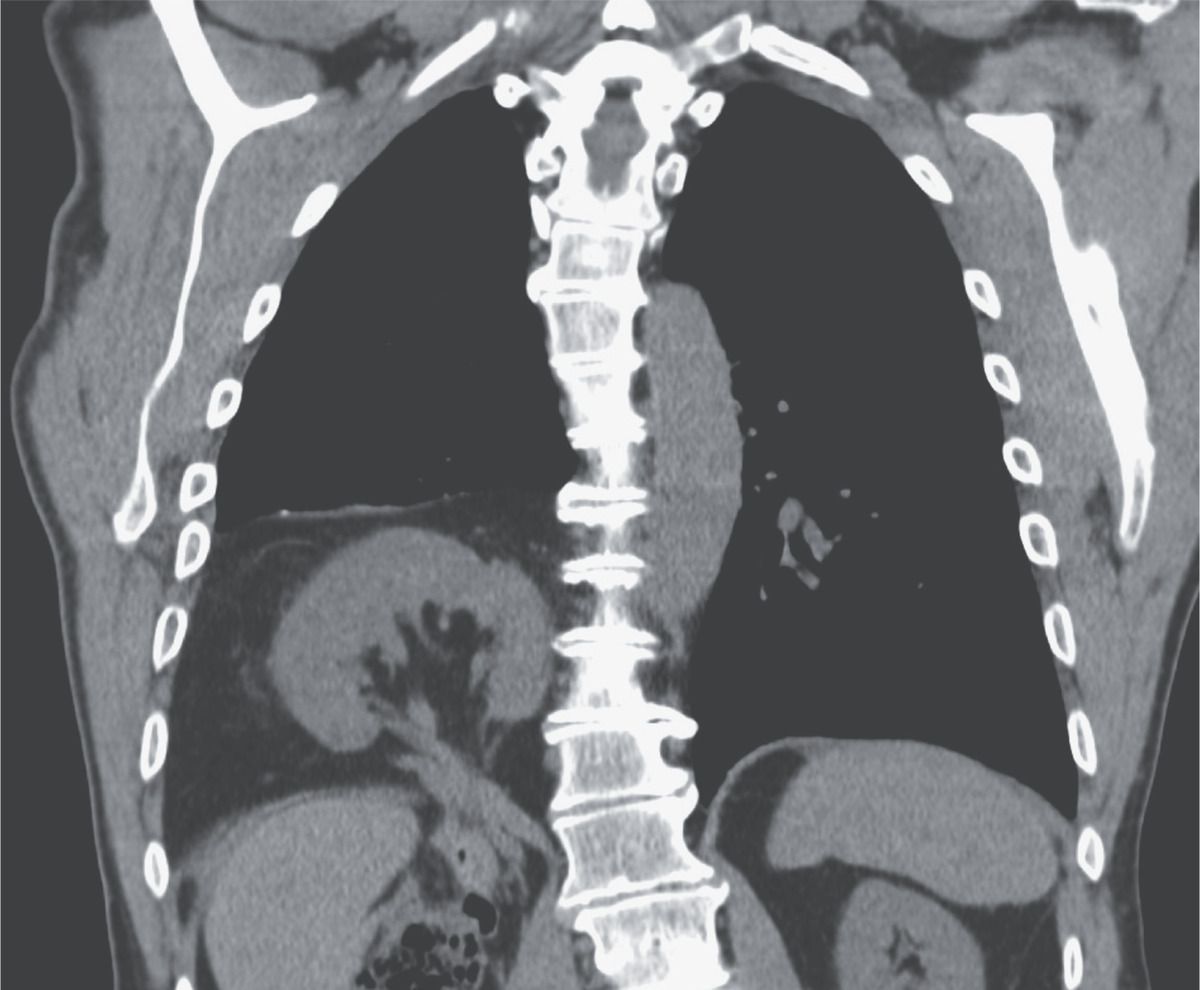

A 77-year-old man presented to the emergency department with nausea, vomiting, and diarrhea. He had no known medical or surgical history and reported no shortness of breath or cough. Physical examination was notable for decreased breath sounds in the lower third of the right side of the chest, and chest radiography revealed an opacity in the right hemithorax. Focused assessment with ultrasonography revealed no evidence of a pleural effusion, but the right kidney could not be identified. A computed tomographic scan of the chest showed a right Bochdalek hernia containing the kidney as well as hepatic flexure of the colon. A Bochdalek hernia results from a congenital posterolateral diaphragmatic defect. It is a common incidental finding, and the hernia is often small and contains only fat. Large Bochdalek hernias containing the kidney, as occurred in this patient, are less common. No specific treatment was initiated for the hernia, and the patient’s gastrointestinal symptoms abated with supportive care.